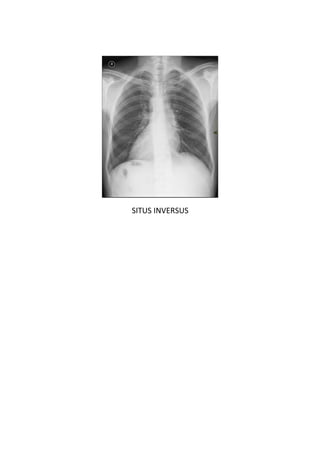

Este documento presenta 7 casos de patología torácica que serán discutidos en una sesión de interpretación radiológica. El objetivo es que los asistentes tomen notas aclaratorias durante la discusión interactiva de cada caso, en lugar de una mera explicación teórica. Los casos incluyen agenesia pulmonar derecha, situs inversus, estridor, neumonía con hemoptisis y enfermedad intersticial. El último caso involucra a un paciente de 86 años con tos y disnea que podría tener una consolidación en la base